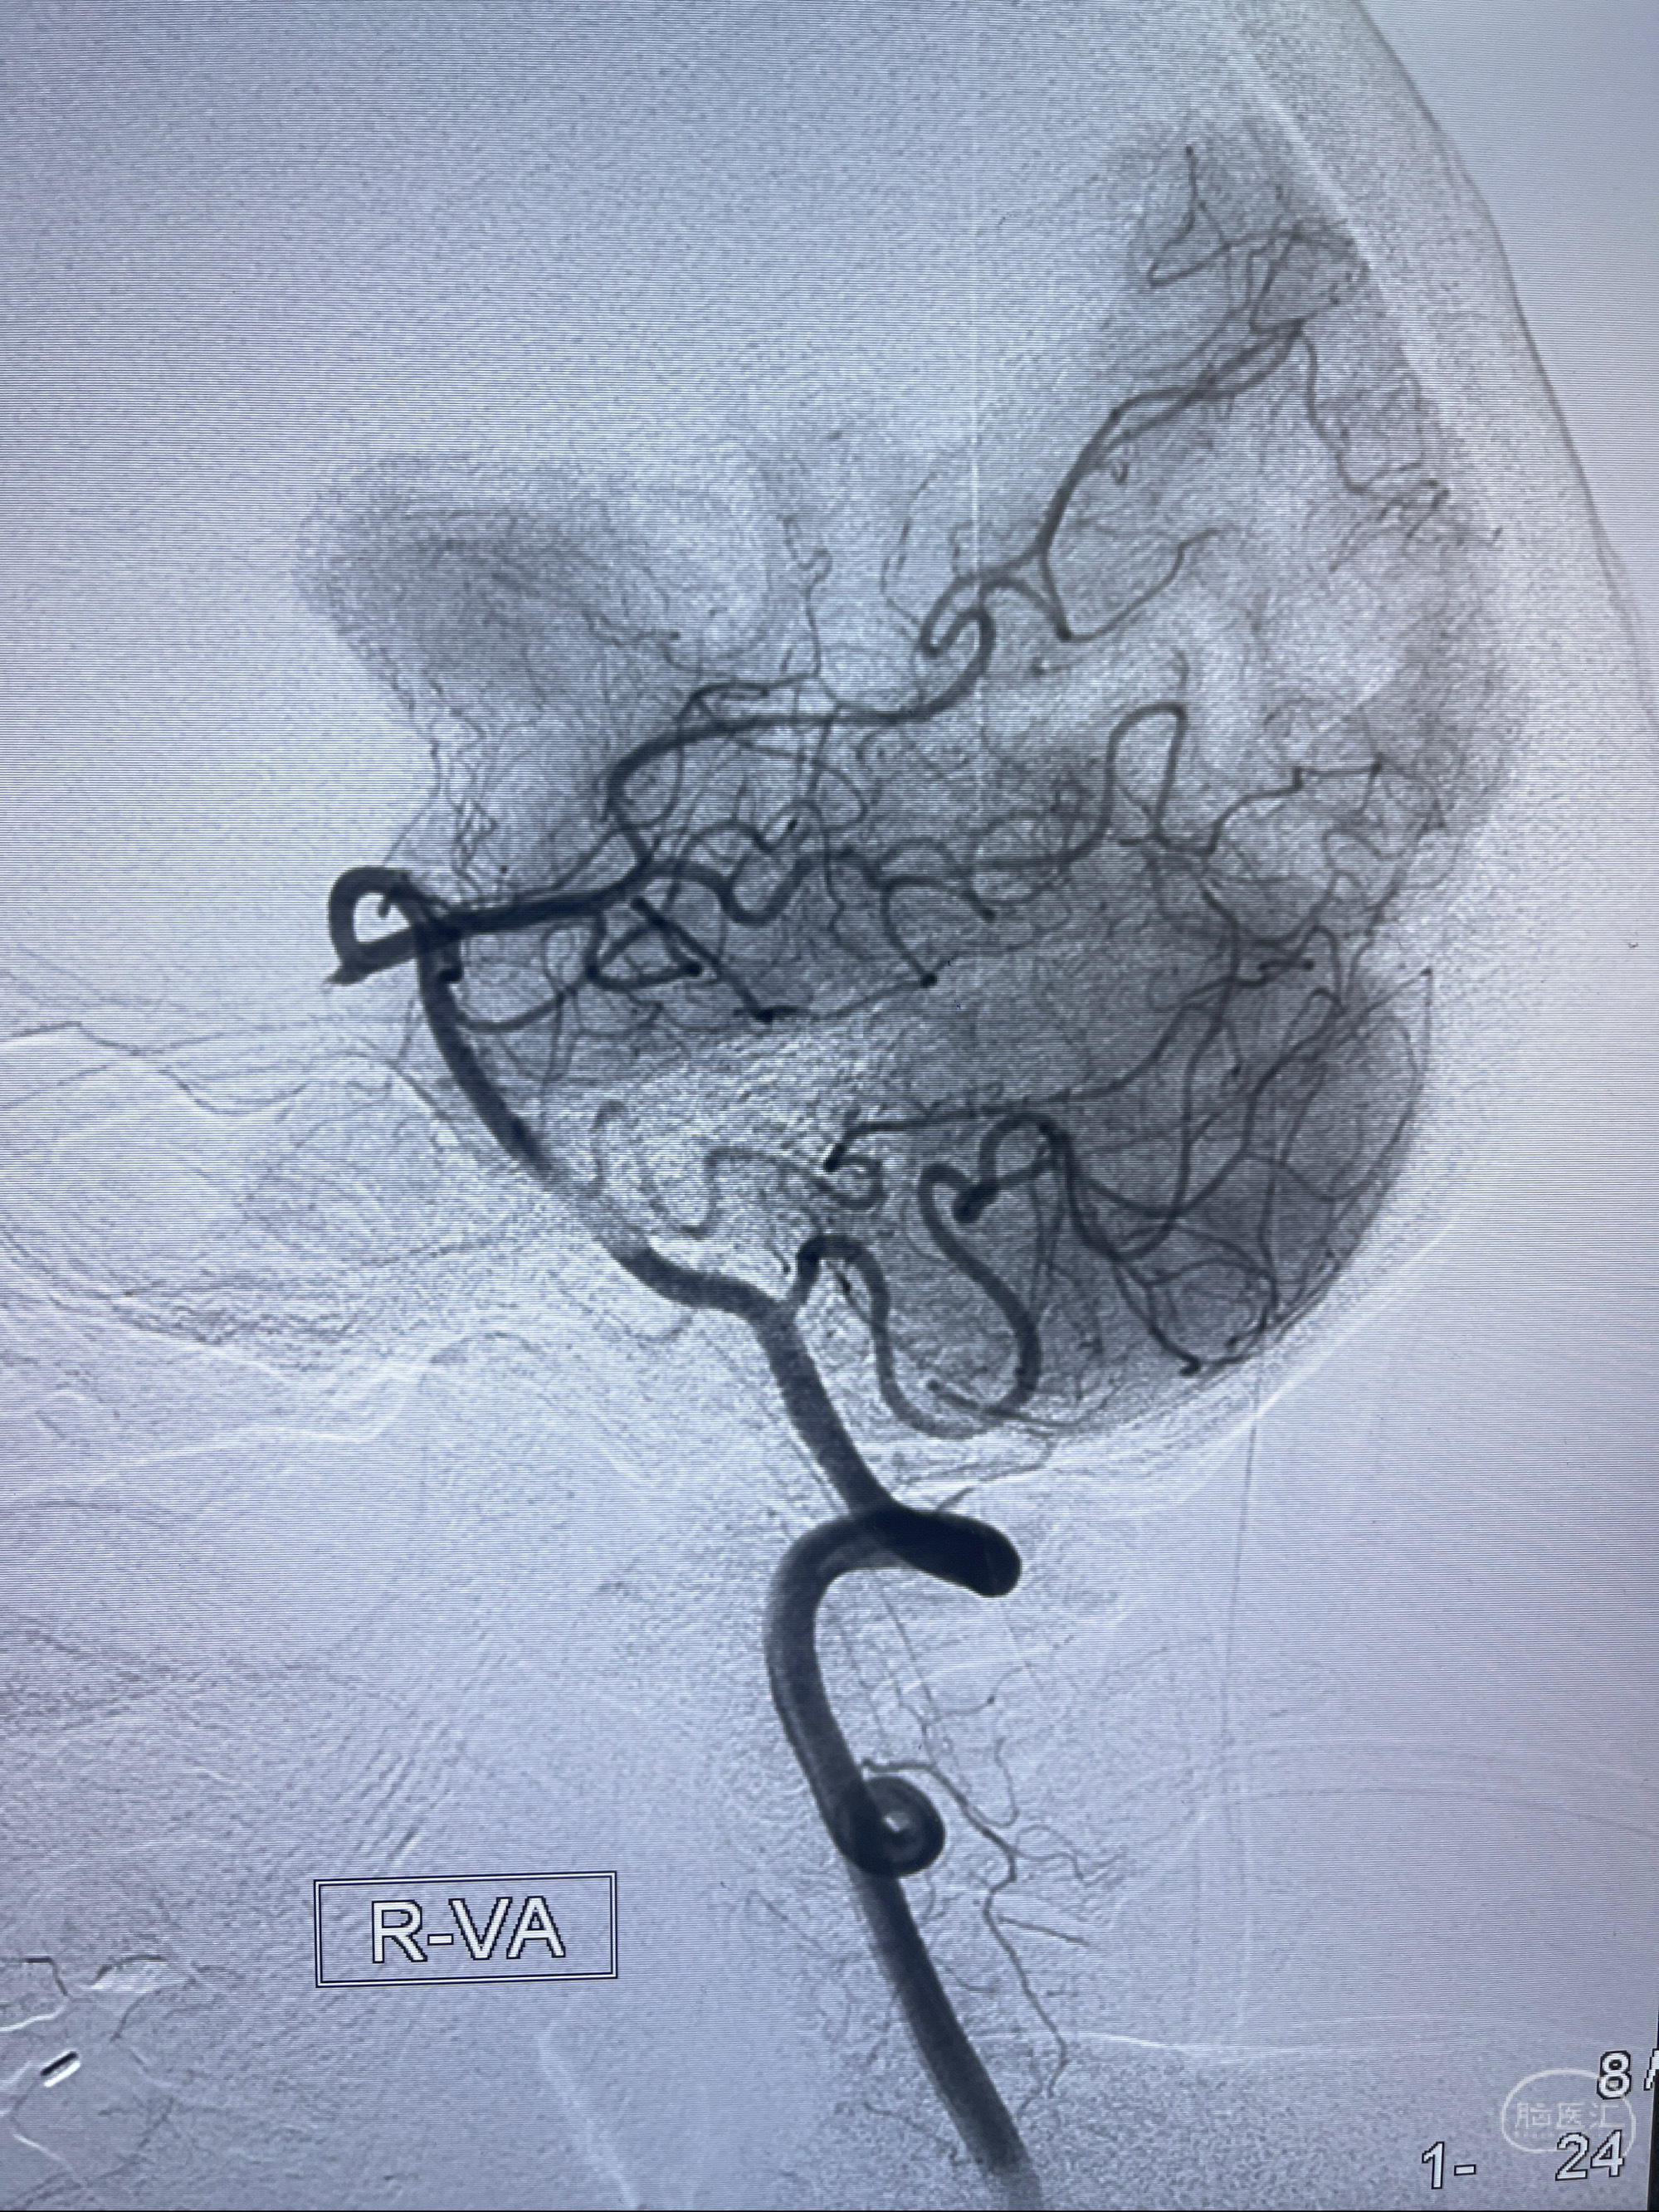

2023-02-02 沛县人民医院 头颅CTA:大脑动脉环发育变异,头颈部动脉粥样硬化,双侧颈内动脉及椎动脉颅内段多发狭窄;

1.双侧脑动脉狭窄

2.腔隙性脑梗死

2023-02-15DSA